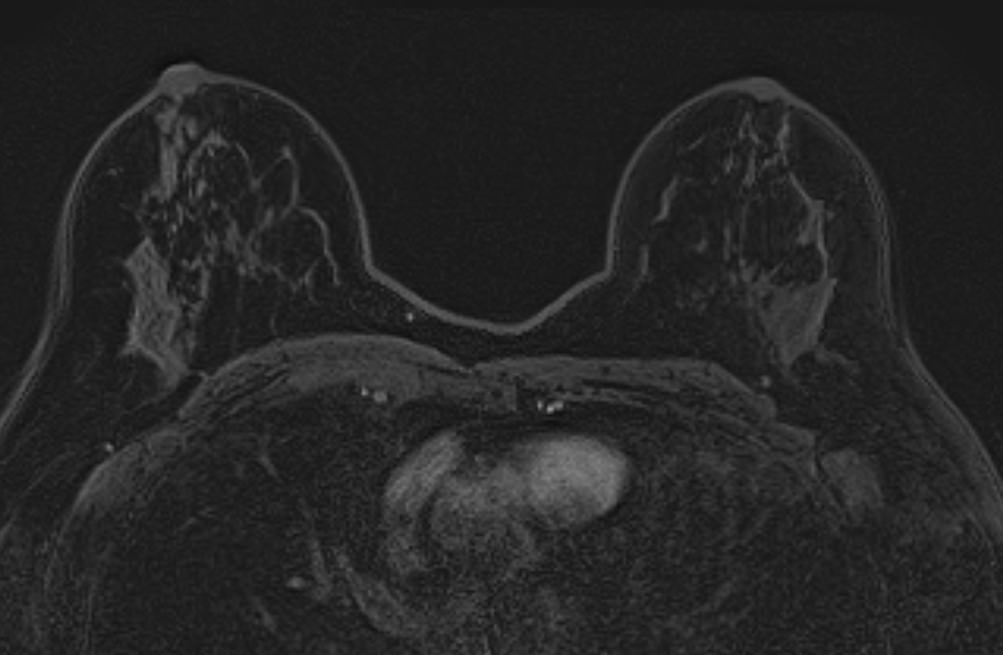

Выполнение МРТ молочных желез без контрастирования возможно для динамического наблюдения состояния имплантатов после пластической операции груди. Во всех остальных случаях во время проведения исследования внутривенно вводится контрастное вещество. Для контрастного усиления применяются препараты на основе солей гадолиния (Магневист, Гадовист и др).

- Для оценки состояния силиконовых имплантов после пластики груди;